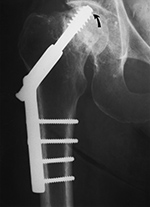

| Left hip cannulated screw fracture |

| 41 year-old man with chronic left femoral neck fracture and fracture of superior cannulated fixation screw. The partially visualized intramedullary nail is for an old femoral shaft fracture. |